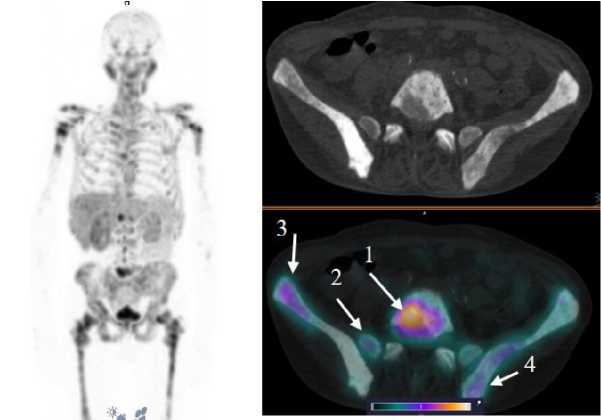

У 4 пациентов, вошедших в исследование, по данным референсных методов исследования, было выявлено метастатическое поражение костных структур, у 2 пациентов — поражение ЛУ. Накопление [99mTc]Tc-HYNIC-PSMA в патологических участках отмечалось у 3 больных с костными метастазами (SUVmax по всем костным очагам 28,57 ± 16,09) и у одного пациента с поражением ЛУ (SUVmax 15,32 ± 8,11). Примеры накопления [99mTc]Tc-HYNIC-PSMA в ПСМА-позитивных костных и лимфогенных метастазах представлены на рис. 4, 5.

Рис. 4. MIP-реконструкция, КТ и совмещенное ОФЭКТ/КТ изображение больного кастрат-резистентным раком предстательной железы с множественными метастазами в кости через 2 ч после инъекции [99mTc]Tc-HYNIC-PSMA. На ОФЭКТ-КТ-изображении стрелкой отмечено накопление РФЛП в патологических очагах: L5 (1) SUVmax 22,8; боковые массы крестца справа (2) SUVmax 9,7; подвздошная кость справа (3) SUVmax 13,4; подвздошная кость слева (4) SUVmax 10,4

Fig. 4. MIP reconstruction, CT and SPECT/CT image of a patient with castrate-resistant prostate cancer with multiple bone metastases 2 hours after injection of [99mTc]Tc-HYNIC-PSMA. Accumulation of radiopharmaceutical in the pathological areas is indicated by the arrow on the SPECT-CT image: L5 (1) SUVmax 22.8; lateral masses of the sacrum on the right (2) SUVmax 9.7; ilium on the right (3) SUVmax 13.4; ilium on the left (4) SUVmax 10.4